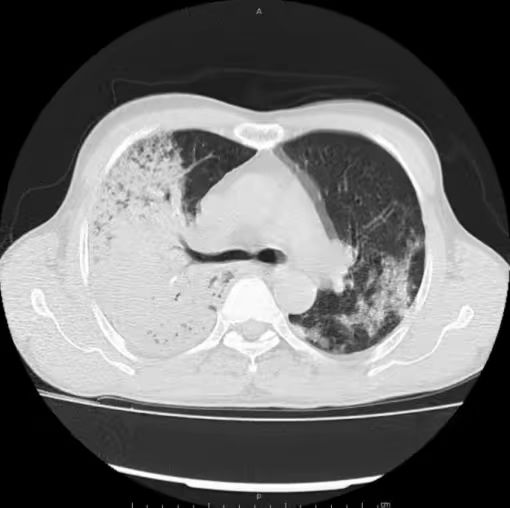

痰、血培养均提示:肺炎链球菌

肺炎链球菌肺炎多为肺泡性肺炎,少数血播肺炎链球菌肺炎好发于老年人及免疫力低下人群,PCT 明显增高。影像上,早期在血管炎的基础上仍能见到按肺小叶充填及闲置的表现(肺泡性肺炎的表现),而大片实变影已不能分辨是否为血管炎(病灶边缘磨玻璃仍可看出血管炎),在肺尖段不会占据整个层面(与铜绿假单胞菌肺炎不同),而在下肺往往表现为齐头并进的特点,分布上多上肺优势。